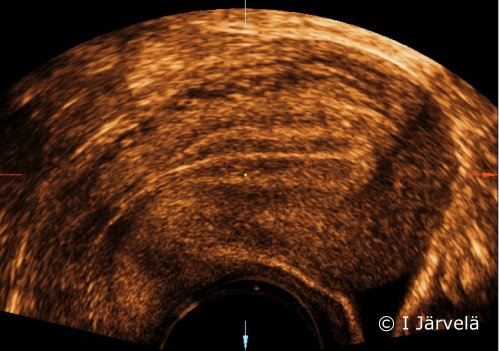

Endometrium in the proliferative phase (ultrasound scan).Oestrogen causes the endometrium to grow and produces the triple-line structure typical for the proliferative phase, as the mucosal layers in the anterior and posterior endometrial walls grow towards each other in the uterine cavity.

Picture: Ilkka Järvelä; text: Dimitrios Scordas